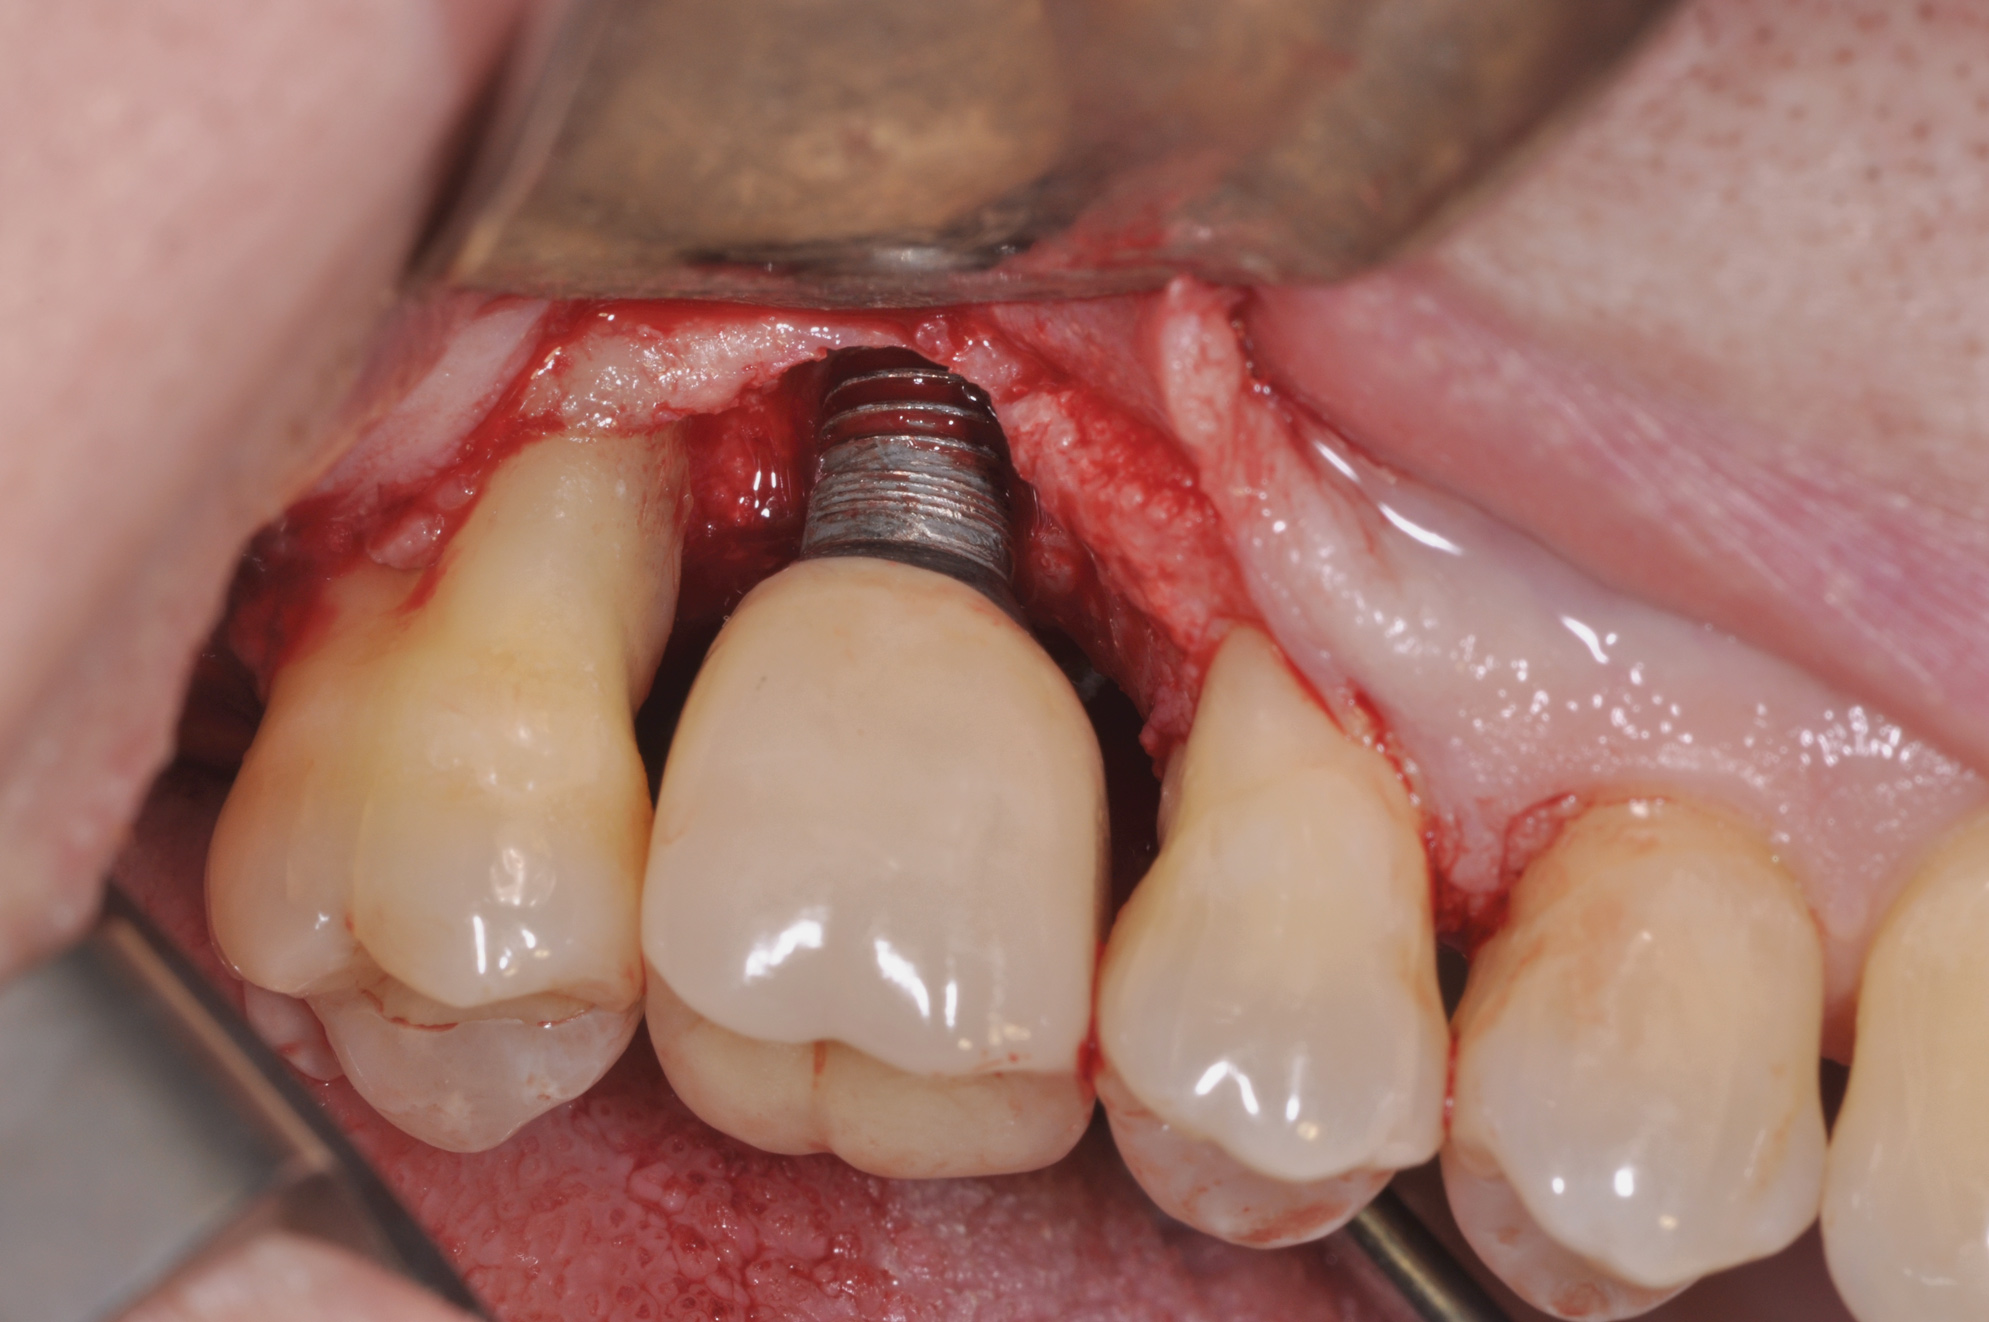

Following the diagnosis of peri-implantitis (Figure 5 and Figure 6), an initial evaluation of the affected implant fixture should be made to establish the rationale for treatment and whether removal of the implant is indicated. Although nonsurgical treatment of peri-implantitis may not always be successful, it should always precede surgical therapy, as this will provide the clinician time to assess the patient's oral hygiene status and response to therapy.22 The primary goal of surgical treatment of peri-implantitis is the decontamination of the denuded implant surface. Multiple surface decontamination protocols have been described in the literature; however, to date, none have shown superiority.23

After implant surface decontamination, the specific surgical approach (eg, access surgery, respective, or regenerative) for each case is heavily dependent on the position of the implant in the oral cavity, as well as the configuration of the peri-implant defect (Figure 7).24 In a recent meta-analysis, an average 2 mm to 3 mm peri-implant probing depth reduction was achieved following surgical intervention.25 Also, implant surface modification (implantoplasty) (Figure 8) was superior to access flap alone. The addition of bone grafts yielded an average of 2 mm of bone fill in defects treated with a regenerative approach. Regenerative treatments may be contraindicated in smokers.

Fig 7. Access flap surgery was performed to assess the defect.

Figure 7